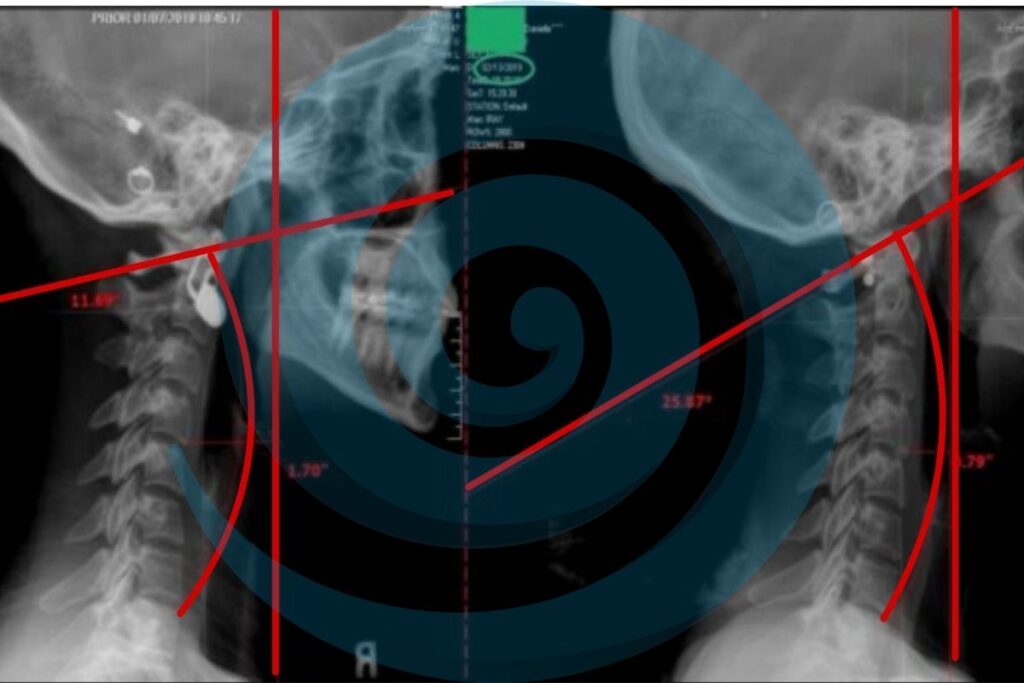

Advanced Imaging Enhancing Chiropractic Care

I went in to see Dr. Norris after having bad migraines and having my arms fall asleep on a regular basis. Dr. Norris was very knowledgeable and explained all of the reasons why I was in this pain and how he can help. He then did 3 separate scans and an X-ray to get a clear treatment plan. I’m very excited to know I will not only be able to feel my progress but we will be able to track it with these scans. We finished with an adjustment that instantly relieved my neck pain and migraine. He popped my rib back in and helped my shoulder. I’m going back Monday to go over the treatment plan. I’m so grateful to finally find someone that can not only help me feel better but also actually fix my back.